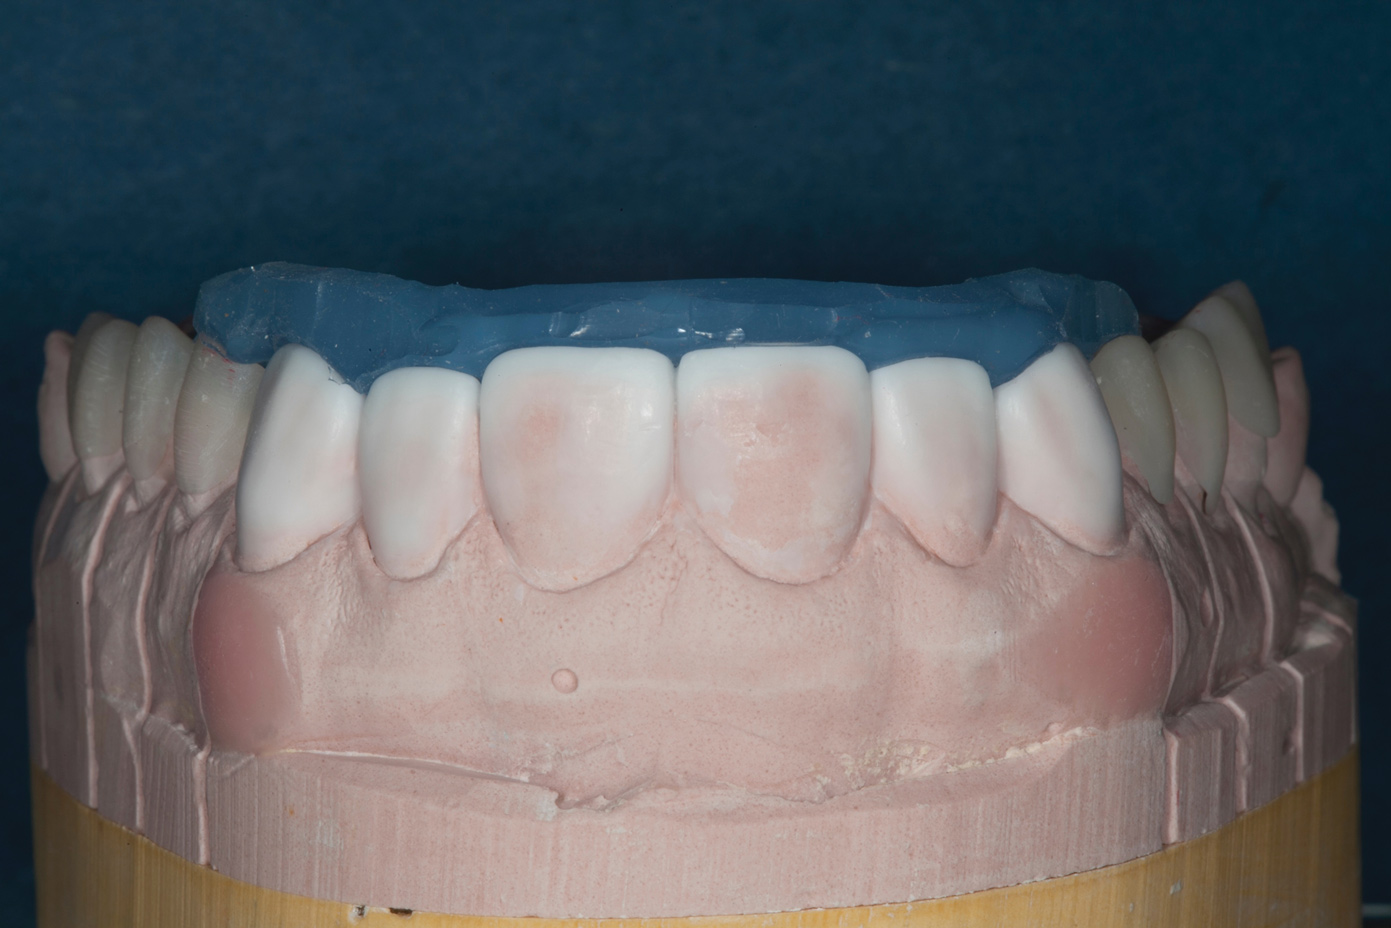

Fig 5. Mounted models showing maximum intercuspation.

Figure 5

Confirmed by the mounted models (Figure 5), the patient's bite was obviously unsatisfactory, but with the orthotic in place, he was completely symptom-free and stable, and therefore, considered to be in acceptable function. However, he was considered to be in occlusal dysfunction without it because he lacked simultaneous, equal-intensity posterior contacts.

Based on multiple factors, the decision was made to close the posterior open bite and create anterior guidance using additive means in the patient's current maximum intercuspation, which was considered equivalent to centric relation. He would then be equilibrated to ensure even, simultaneous posterior contacts and canine guidance.